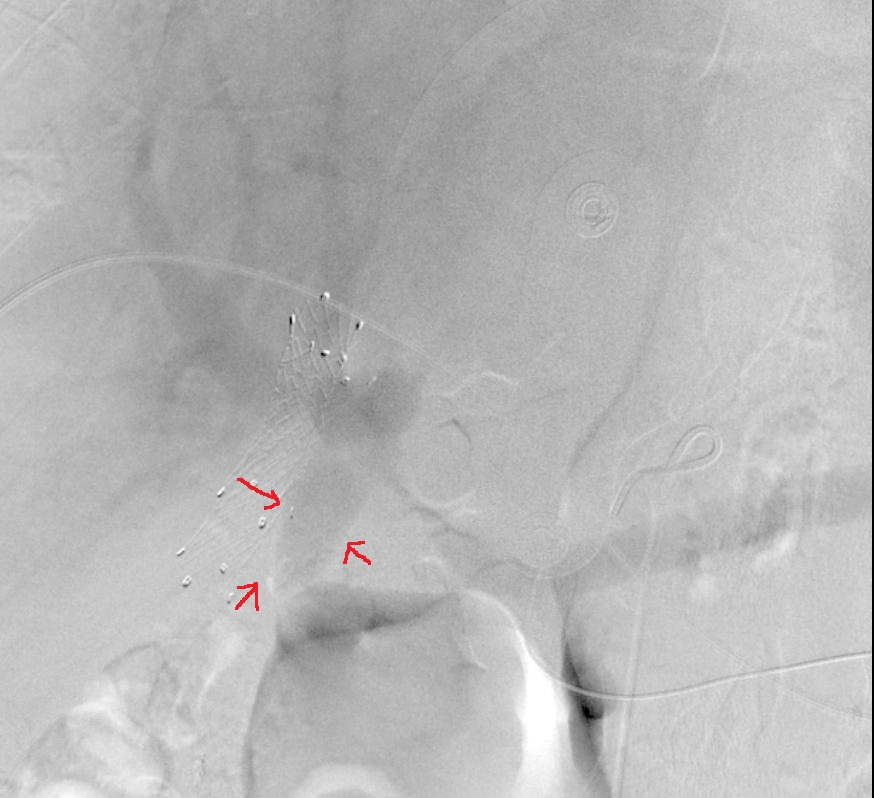

间接门静脉造影显示更清楚的紧邻胆道支撑架的门静脉瘤

经肝门静脉造影显示胆道支撑架旁的门静脉瘤

门静脉支撑架置入

过支撑架网眼弹簧栓子栓塞

弹簧栓子填塞术后

改变投照角度造影